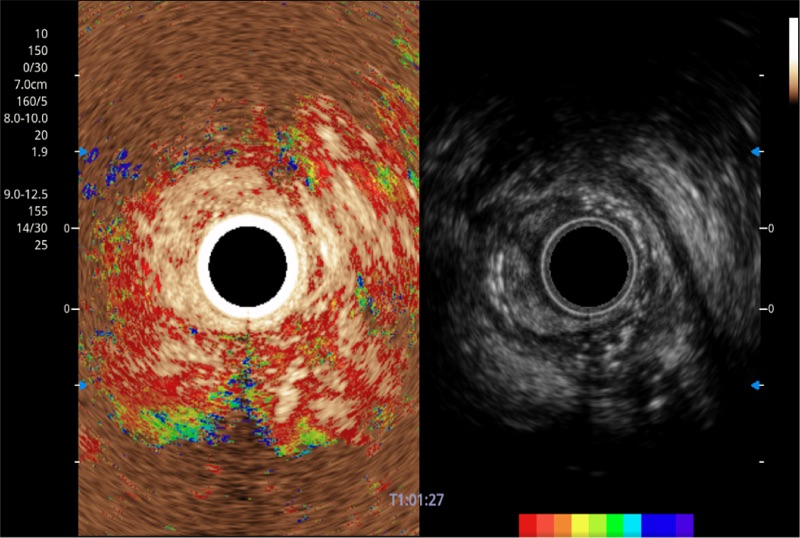

可人为将灰阶图像转变成彩色的显示方式,增强人眼对于不同回声强度的敏感度,主观上增加了图像分辨率